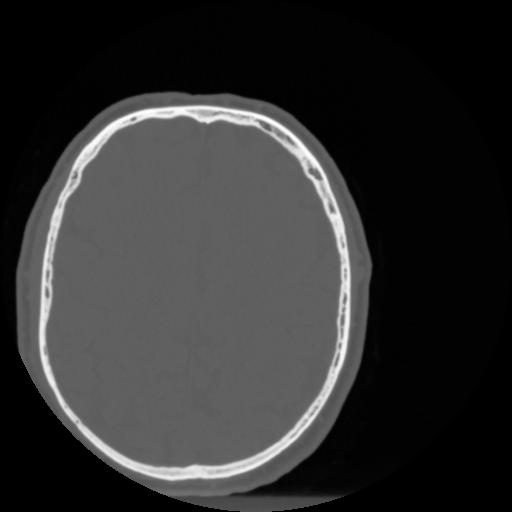

4 CEREBRO,,Vol,0.5,CEREBRO,,